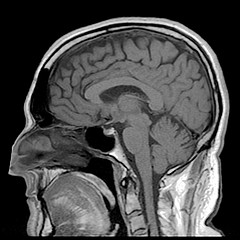

Neuroscience is finding itself at the center of a growing controversy in the courtroom. Will judges weigh biological evidence that could suggest future dangerous activity or impaired control differently and how will that affect systems of sentencing and determinations of guilt in the court? This biological evidence could be considered “mitigating” or decreasing a sentence (their brain is broken, it’s not their fault) or it could be “aggravating” (their brain is broken and they will offend again) and increase a sentence. To test whether Judges would reason differently after receiving biological evidence in a trial, a group has conducted a study on U.S. state trial judges.

Judges were presented with a mock case (based loosely on an actual case Mobley v. State), in which a man beat a restaurant manager until he had permanent brain damage when he refused to turn over money from the register.  The judges were randomly assigned to four conditions: 2 presenting parties (prosecution or defense) and 2 biomechanism groups (absent or present). They were presented identical testimony from a psychiatrist diagnosing the man as a psychopath. Judges in the biomechanism present group heard testimony from a neurobiologist stating that the man had a genetic variation and atypical brain function which predisposed him to violent behavior. In the prosecution condition, prosecutors argued that this evidence should be considered aggravating because he likely posed a continued threat to society. In the defense condition, it was argued that the evidence be considered mitigating because the defendant had a more difficult time controlling his impulses due to his genetic abnormalities. These conditions should allow the researchers to understand how biomechanistic evidence affects judge’s reasoning in sentencing.